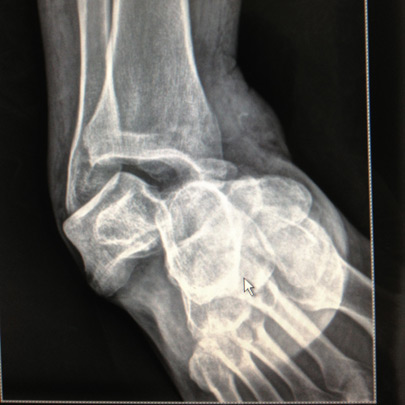

Fracturas y luxaciones

Cirugía de tobillo